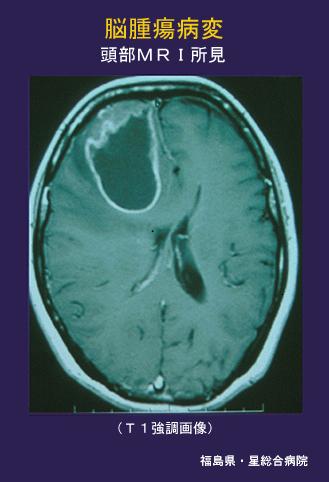

A case of Turcot syndrome associated with hereditary non polyposis colorectal cancer.

Fukushima Pref., Hoshi General Hospital (Dr. 権田, 野水)

[ Image ID:4465 ]

Turcot syndrome/

MRI

40 -